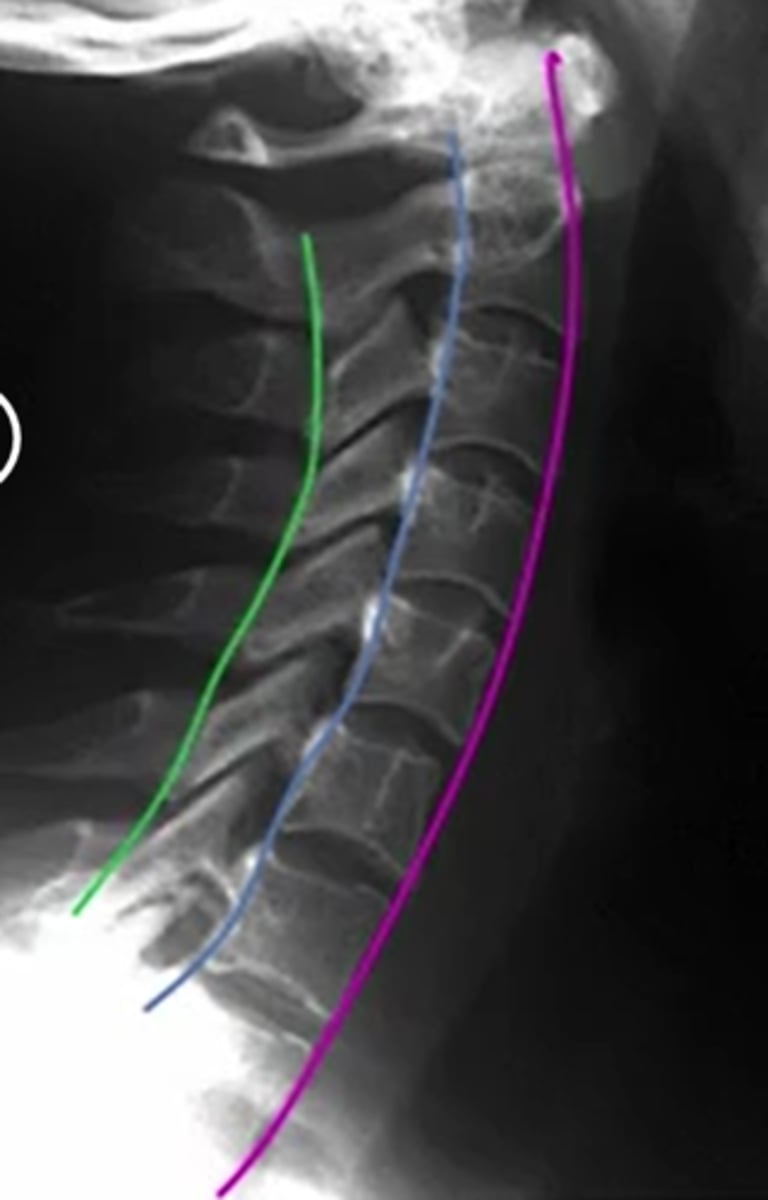

what does the spinolaminar line, anterior and posterior vertebral line look like

purple anterior

posterior: blue

spinolaminar line: green

between blue and green is the spinal cord